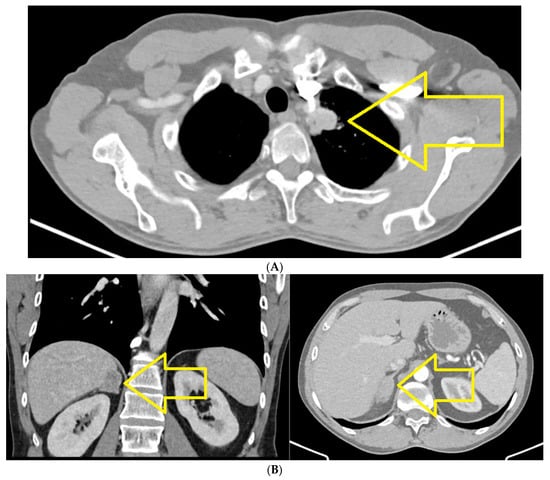

2. Case Report